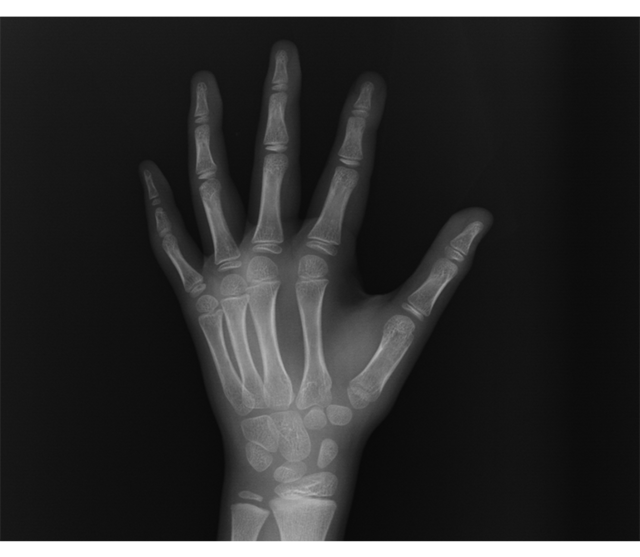

x-ray로 TW3방식을 통해 Rus 접수와 Z-score를 계산하여 정확한 뼈나이를 산출하게 됩니다.

TW3는 기존에 존재하던 여러 골 연령 판정이론보다 더 객관적이고, 더 수학적인 배경을 가지고

골성숙을 평가하는 방법입니다. 골연령 판정과 성인 신장의 예측이론에 관해

가장 신뢰도 높은 성장분석법으로 인정되고 있습니다.